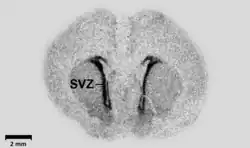

La barre d'échelle noire (en bas à gauche de l’image) correspond à une longueur de 2 mm. Elle est utilisée notamment pour observer le rôle de l'hypothalamus.

L’autoradiographie est une technique d'imagerie d'émission réalisée à partir d'une source radioactive placée au contact d'une émulsion ou d'un film photographique[1]. Comme l'indique le préfixe auto-, à la différence de la microradiographie, la source de rayonnement n'est pas une source externe (de rayons X par exemple), mais elle est incluse dans l'échantillon dont on produit une image[1]. En cela elle diffère fortement des techniques radiographiques classiques qui sont des techniques d'imagerie de transmission.